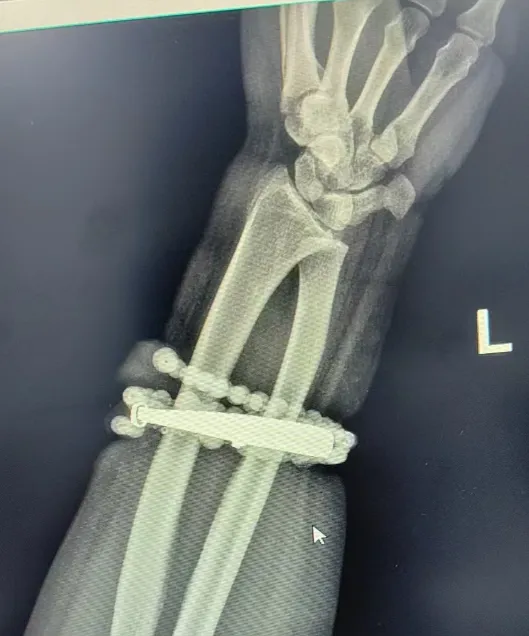

戴了十年没摘的手镯、串珠竟长进了肉里,还发炎了!近日,闽东医院创伤骨科、手显微外科就接诊了这样一位患者。

33岁的龚女士(化名)手腕上的银手镯和串珠戴了近十年,几乎从未摘下来过。随着时间推移,龚女士的体重也有所增加,手腕逐渐被勒得紧绷,但她并未在意。

然而,就在两周前,龚女士的情况急转直下:手腕不仅疼痛加剧,还出现了明显的红肿,甚至有脓液渗出。她这才惊觉——手镯和串珠,已经有一部分“长”进了肉里,根本取不下来了!

“这是典型的首饰长期压迫、摩擦,加上细菌感染,引发的慢性炎症和肉芽组织增生。”医生介绍,此时,手镯和串珠已经成了一个不断刺激皮肤、污染伤口的“病灶”,如果不尽快手术取出,感染可能进一步扩散,甚至危及生命或影响手臂功能。

经过一个多小时的手术,医生们将手镯和串珠从厚厚的增生组织中完整剥离出来。目前,龚女士恢复良好,已顺利出院。